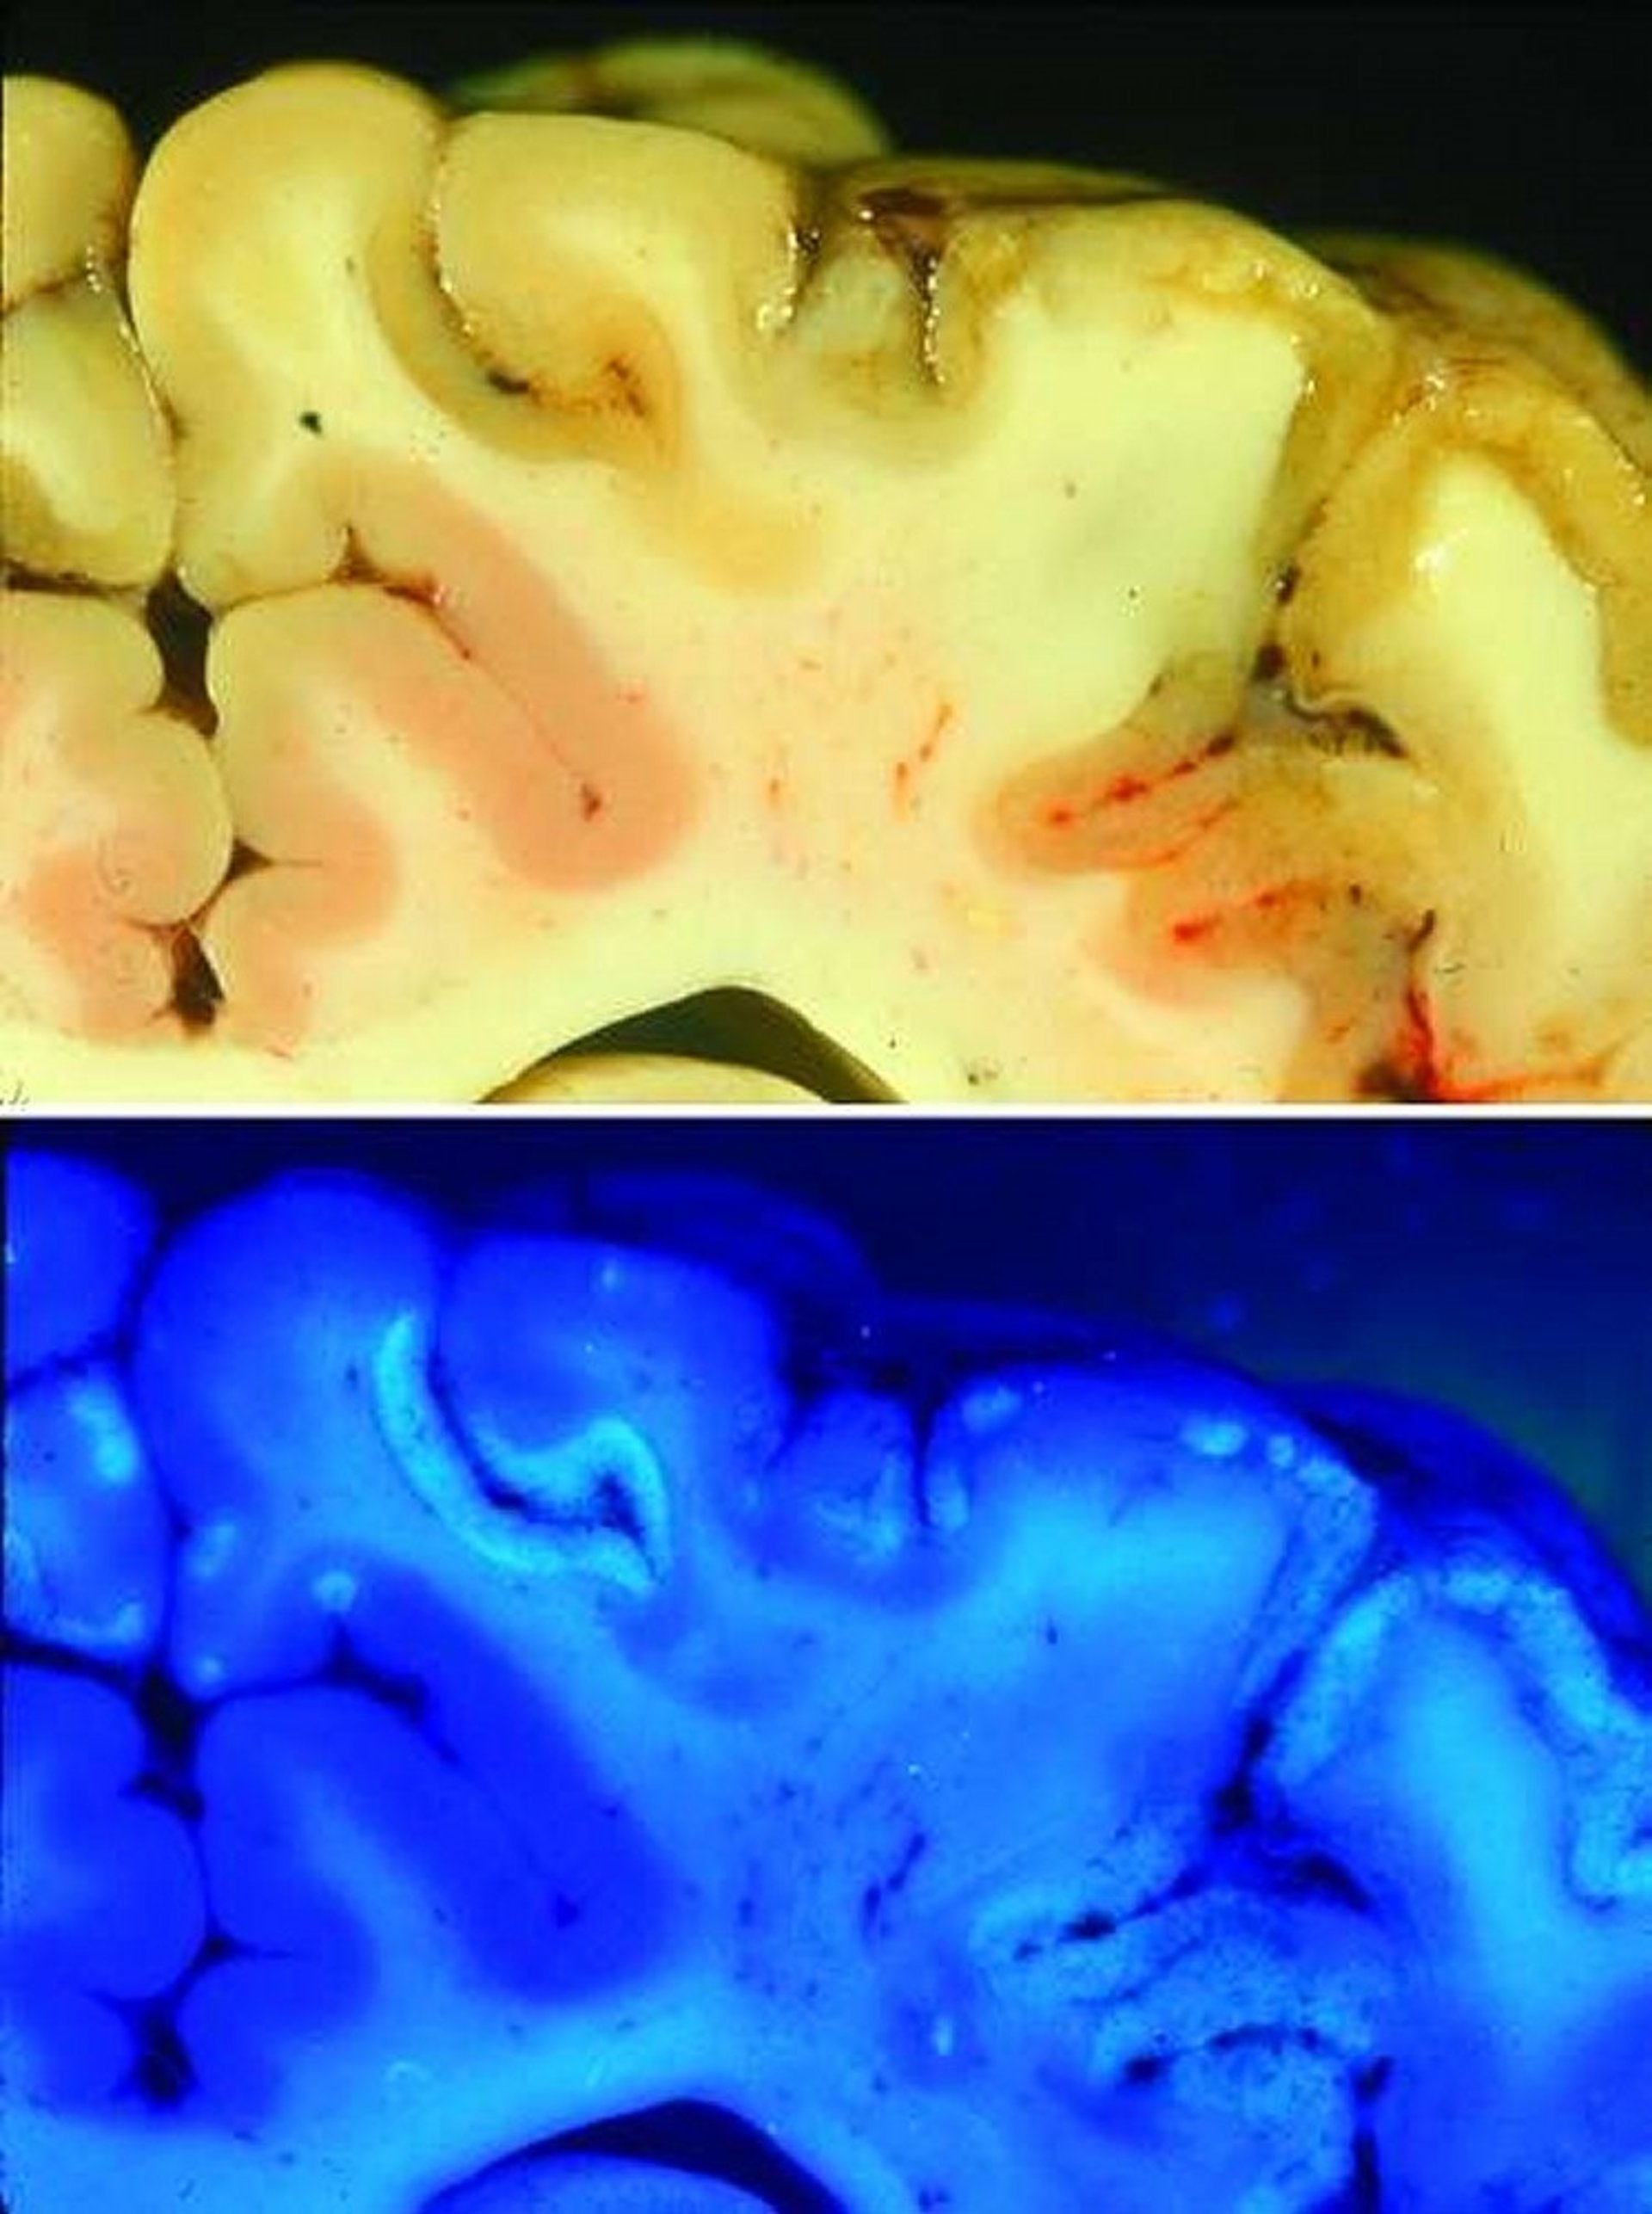

Transverse section of the dorsal parietal cortex of a feedlot steer that had polioencephalomalacia. Upper panel—macroscopic view under ambient illumination. Affected segments of the cortical gray matter have a yellowish discoloration and irregular contours. Lower panel—same section viewed with ultraviolet (366 nm) illumination. Affected segments and foci of the cortical gray matter have a bright, light blue hue compared with the darker blue of adjacent, normal cortex.

Courtesy of Dr. Daniel H. Gould.